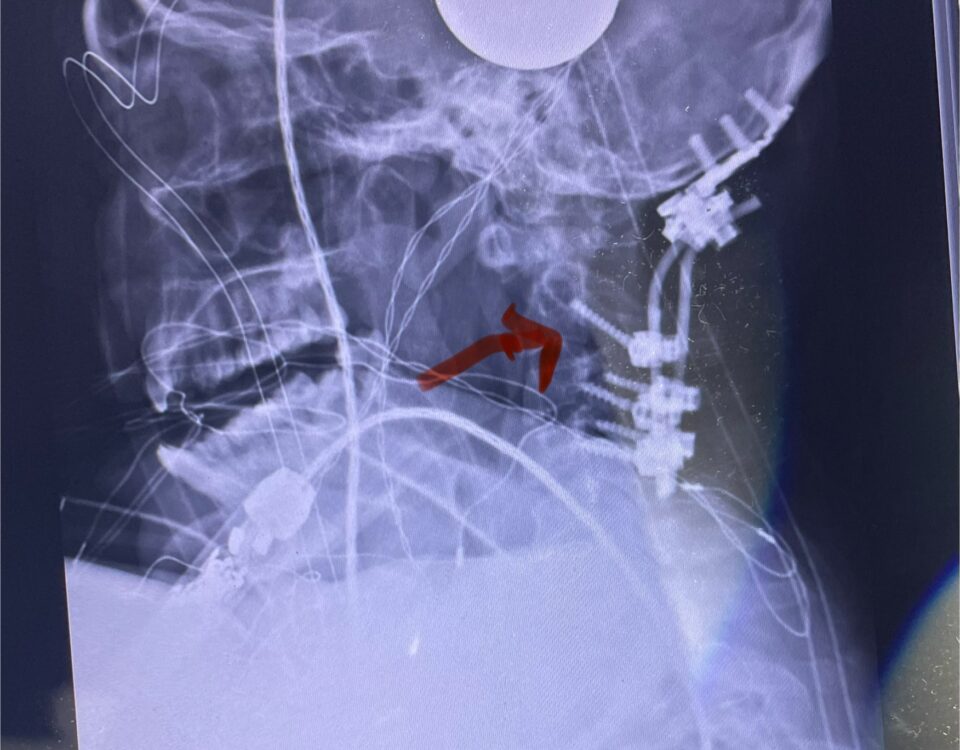

Patients may require an occipital-cervical fusion for both cranio-cervical and atlanto-axial instability, depending on the anatomy. Patients who have long segment posterior cervical fusions can sometimes […]